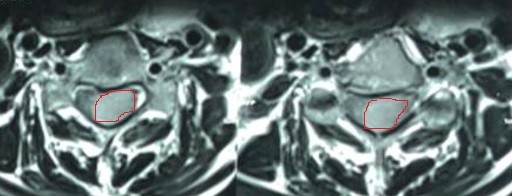

ورم سحائي بالنخاع الشوكي العنقي

meningioma of the cervical spinal cord

An image of an MRI scan of a 62-year-old female patient suffering from stiff partial quadriplegia, which led to movement impairment. And he found a meningioma pressing on the spinal cord in a way that the tumor occupied the nerve canal almost, shaded in red against the fifth cervical vertebra. And the pictures during the microscopic surgery to remove it, showing its location and size in yellow, and the recovery of the cervical nerves and cervical marrow from pressure, shown in green. The patient recovered after the successful surgery.